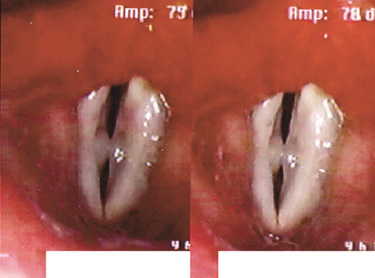

성대낭종은 선천성과 이차적인 후천성에 의해 발생하며 성대결절과 같이 음성을 과도하게 사용한 경우 자주 나타납니다.

후두미세수술을 시행하며 성대점막의 유착과 강직을 방지하기 위해 PDL레이저 성대수술을 병행하여 시행하기도 합니다.

성대낭종의 수술은 낭종의 주머니까지 모두 제거하는 것이 재발률을 줄일 수 있습니다.